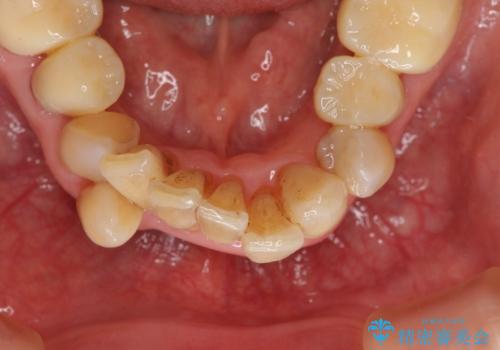

- 上顎前歯の黒ずみの改善、下顎前歯の十度なガタつき、矯正治療とセラミック治療を含む全体的な治療を希望され来院されました。

銀歯を高強度の仮歯に替えたのち、下顎前歯のみの部分矯正→全体的なマウスピース矯正治療(インビザライン)→最終的なセラミック治療と治療を進めます。